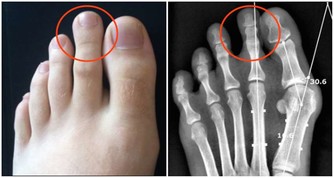

外陰瘙癢:婦科炎症

女性如果出現外陰瘙癢的症狀,則要警惕滴蟲、白色念珠菌感染等婦科炎症。